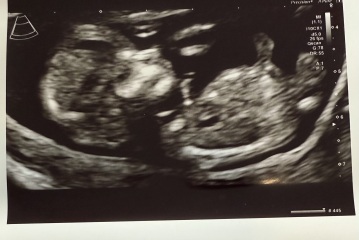

Rainbowbaby25 · 01/06/2025 11:54

Mixed opinions on other forums.

Girl because of bladder position and forked nub, also under 30 degrees and only slightly upward.

Others saying boy because of skull and the nub pointing more up then parrell but not to spine.

12+4 scan